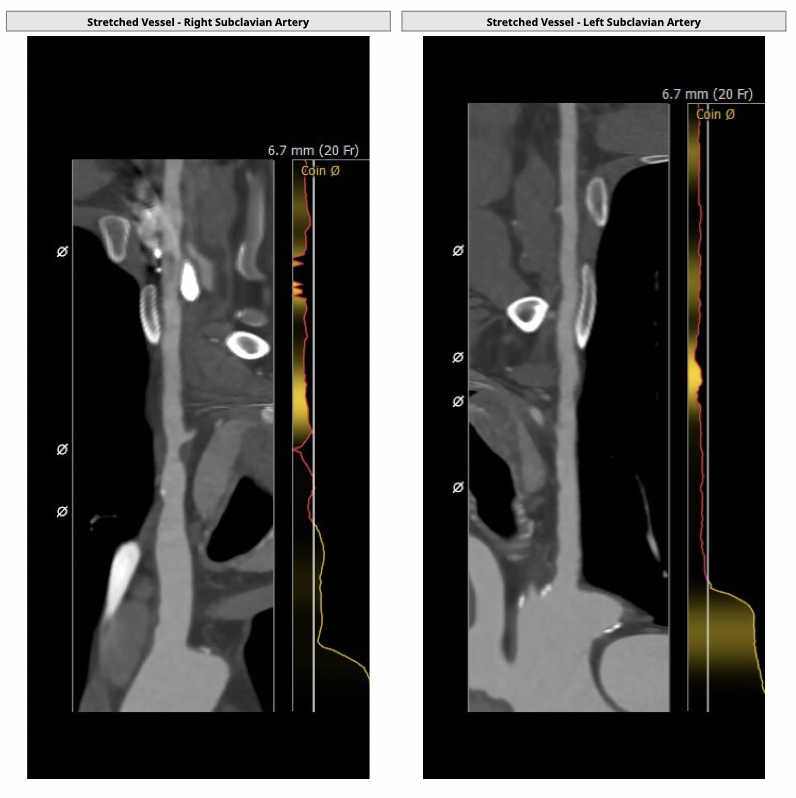

①患者因规律透析导致钙磷代谢紊乱,外周血管斑块钙化严重,最狭窄处仅2.8mm,通路建立难度极大(左右颈动脉均不符合入路条件);

②主动脉根部钙化较轻,瓣叶肥厚,各交界缘不同程度粘连,瓣膜释放后具有瓣周漏风险;